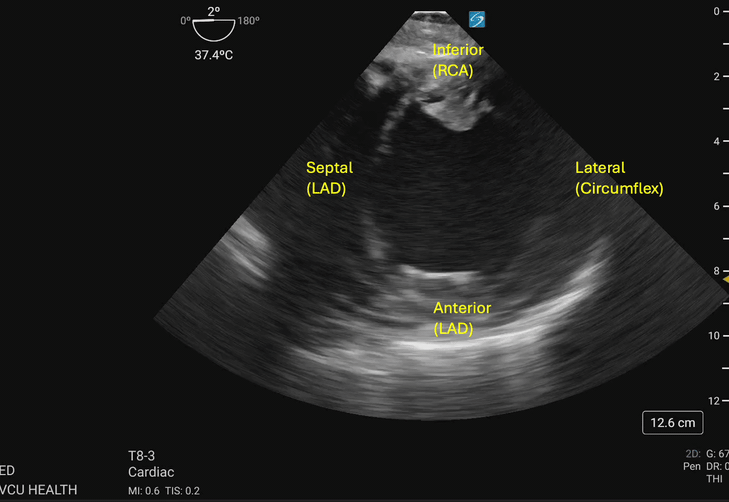

In the focused approach utilized in resuscitative TEE, evaluation of regional wall motion abnormalities in the major vascular territories of the left anterior descending (LAD), left circumflex (LCx), and right coronary artery (RCA) can be performed using the TG SAX view at the level of the midpapillary plane. To obtain this view, the operator will advance the TEE probe to an approximate depth of 40cm from the incisors, set the omniplane angle between 0-20 degrees, and anteflex the probe sufficiently to obtain the view demonstrated in Figure 1 and Figure 2. With slight adjustments in the depth of insertion further assessment of the base and apex of the left ventricle can be obtained.

Hypokinesis or akinesis of the left ventricular myocardium segments can indicate tissue ischemia or infarction in specific vascular territories (Figures 3a and 3b). The RCA supplies the myocardium of the inferior wall of the left ventricle. On TEE, the inferior wall is located closest to the probe footprint, since the probe is coming from the stomach located inferior to the heart. The LAD supplies the myocardium of the anterior and septal portions of the left ventricle. The circumflex artery supplies the lateral portion of the left ventricular myocardium and will be shown on the rightward aspect of the ultrasound image.4

Figure 3a. Walls of the left ventricle as seen on TGSAX with vascular territories. The left ventricle here demonstrates global hypokinesis rather than pathology isolated to one vascular territory. Image courtesy of Lindsay Taylor, MD.